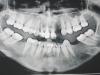

sokoir Опубликовано 27 февраля, 2008 Поделиться Опубликовано 27 февраля, 2008 Добрый день! Подскажите, пожалуйста, в сложной ситуации. Была удалена верхняя двойка (сохранить было никак - треснул корень под коронкой). Надеялась, что можно будет поставить консольный мостик на тройку. Сделала панорамный снимок, а там темные пятна. У меня была киста на единичке, но я как-то боялась ее оперировать, теперь все разрослось? Посмотрите, пожалуйста, снимок. Все очень ужасно? Как мне теперь можно будет протезироваться и что теперь делать??? Заранее спасибо. Ссылка на комментарий

Штаматолог Опубликовано 27 февраля, 2008 Поделиться Опубликовано 27 февраля, 2008 боюсь, а что делать? меня больше кисты на зубах пугают, не хочется все передние зубы-то вырывать Месяц назад. Но когда еще консультировалась с врачами перед удалением, мне сказали, что имплантант не мой вариант и мне лучше мост. Мне кажется, что мост я "проще" перенесу. Ваш вариант - это перелечивание всех необходимых зубов наверху спереди (по этому снимку точнее трудно что-то сказать), оротодонт, имплантация и протезирование. Остальное - компромиссы, которые решат какую-то сиюминутную проблему, но к "зубному здоровью" не приведут, а приведут к более серьезным тратам в будущем и "прописке" у стоматолога на долгие годы. Как иногда почитаешь отзывы пациентов - советую доктора Х., чудо-доктор, лечусь уже у него 10 лет... Это про вас - будете профессиональным пациентом.ЗЫ. Консоль в переднем отделе - очень плохо. Ссылка на комментарий

Штаматолог Опубликовано 27 февраля, 2008 Поделиться Опубликовано 27 февраля, 2008 В том-то и проблема, что их (передние зубы) не перелечить. Нервы удаляла еще в детстве, много лет назад и перепломбировать каналы не удается, пытались несколько раз, врачи говорят цемент В умелых руках с хорошим оборудованием это не самая страшная проблема, ультразвуком цемент (если это он) вполне можно распломбировать. Вы где живете?Да и странная логика у ваших врачей, импланты ставить нельзя, на зубах типа "кисты", каналы не перелечить... Конечно, самое лучшее решение забабахать мост на такие зубы. Ссылка на комментарий

kromanion Опубликовано 28 февраля, 2008 Поделиться Опубликовано 28 февраля, 2008 В том-то и проблема, что их (передние зубы) не перелечить. Нервы удаляла еще в детстве, много лет назад и перепломбировать каналы не удается, пытались несколько раз, врачи говорят цемент Имплантация была бы самым грамотным решением, но соседние зубы все равно перелечивать надо. Сделать это не так сложно, но если совсем все трудно, то можно предложить хирурическое лечение "кист". В этом случае можно все передние зубы закрыть коронками, предварительно убрав все пломбы и вкладки из каналов, и вместо левой двойки сделать консоль. Эстетически, правда, это может получиться не очень, но надо смотреть что сейчас в полости рта. Я не люблю консоли, но в данном случае проблем с надежностью не должно быть Ссылка на комментарий